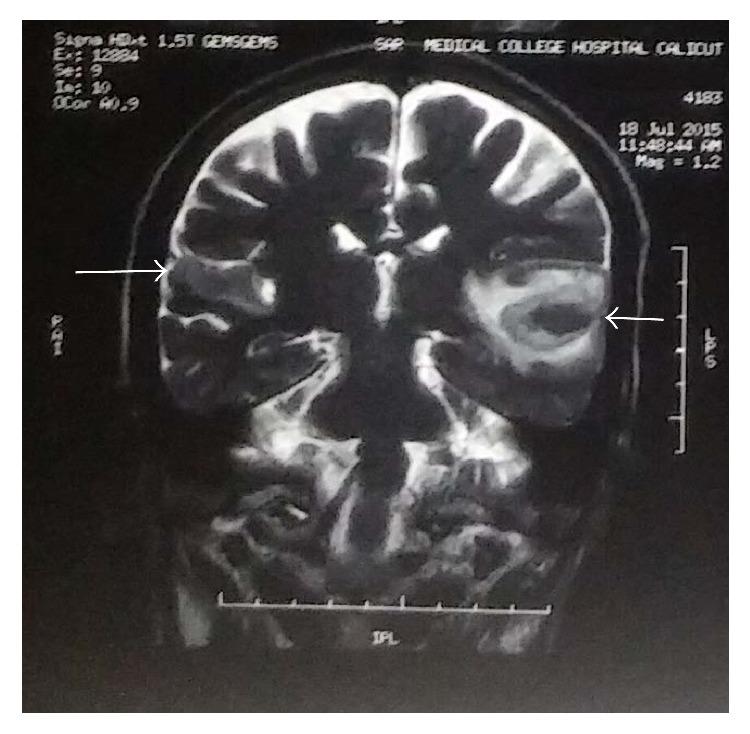

We report the case of a 58-year-old male who presented with an episode of seizure and abrupt onset hearing loss. Neuroimaging revealed acute infarcts in bilateral Heschl gyri. Objective tests of peripheral auditory function were essentially normal and a diagnosis of cortical deafness was made.

我们报告了一例58岁男性病例,该患者出现一次癫痫发作并伴有突发听力丧失。神经影像学检查显示双侧颞横回急性梗死。外周听觉功能的客观测试基本正常,遂诊断为皮质聋。